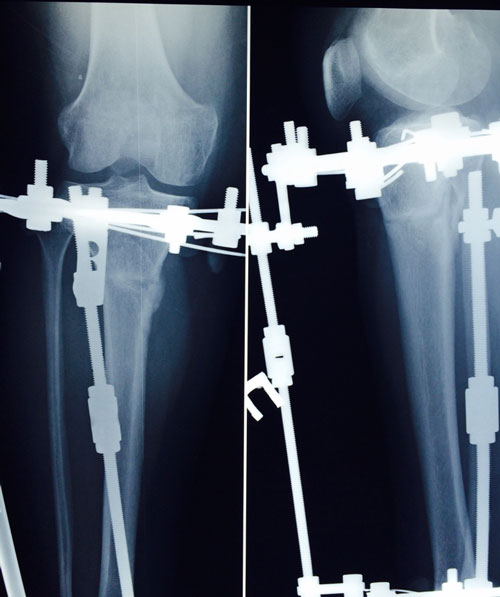

рентген в 90 дней.

Здравствуйте, Б.! Сращение идёт хорошо, но Вам ходить ещё месяц. в 120 дней ждём рентген.